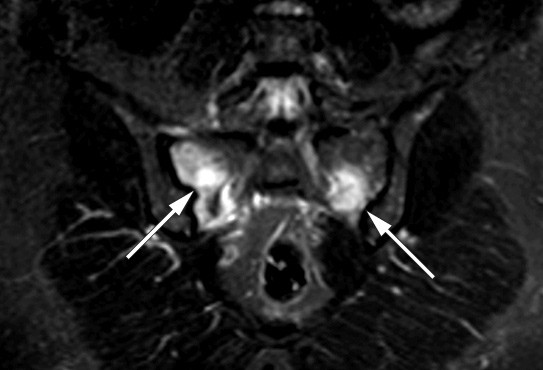

Treatment consists of discontinuing iron saccharide supplements and optionally administering supplements of phosphate and vitamin D orally (2). Fortunately, the renal tubular dysfunction and osteomalacia appear to be reversible, but serious bone deformations may be permanent. At a check-up five months after termination of all iron supplements, the patient was recovering. MRI showed regression of pathological changes (right image). However, the patient still needs treatment for iron deficiency anaemia and is now receiving a different type of iron supplement intravenously. Her need for transfusion varies somewhat, depending on how often she receives iron.